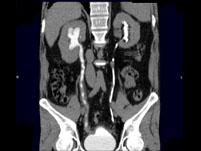

问题 男,47岁,腰痛、腰胀2月余伴低热、乏力,如影像资料所示,下列哪项说法正确 ( )

选项 A.右侧输尿管多发性狭窄,呈“串珠样”改变 B.右侧输尿管多发性生理性狭窄 C.右侧肾盂轻度积水 D.考虑为右输尿管占位病变 E.考虑为右输尿管结核

答案 ACE